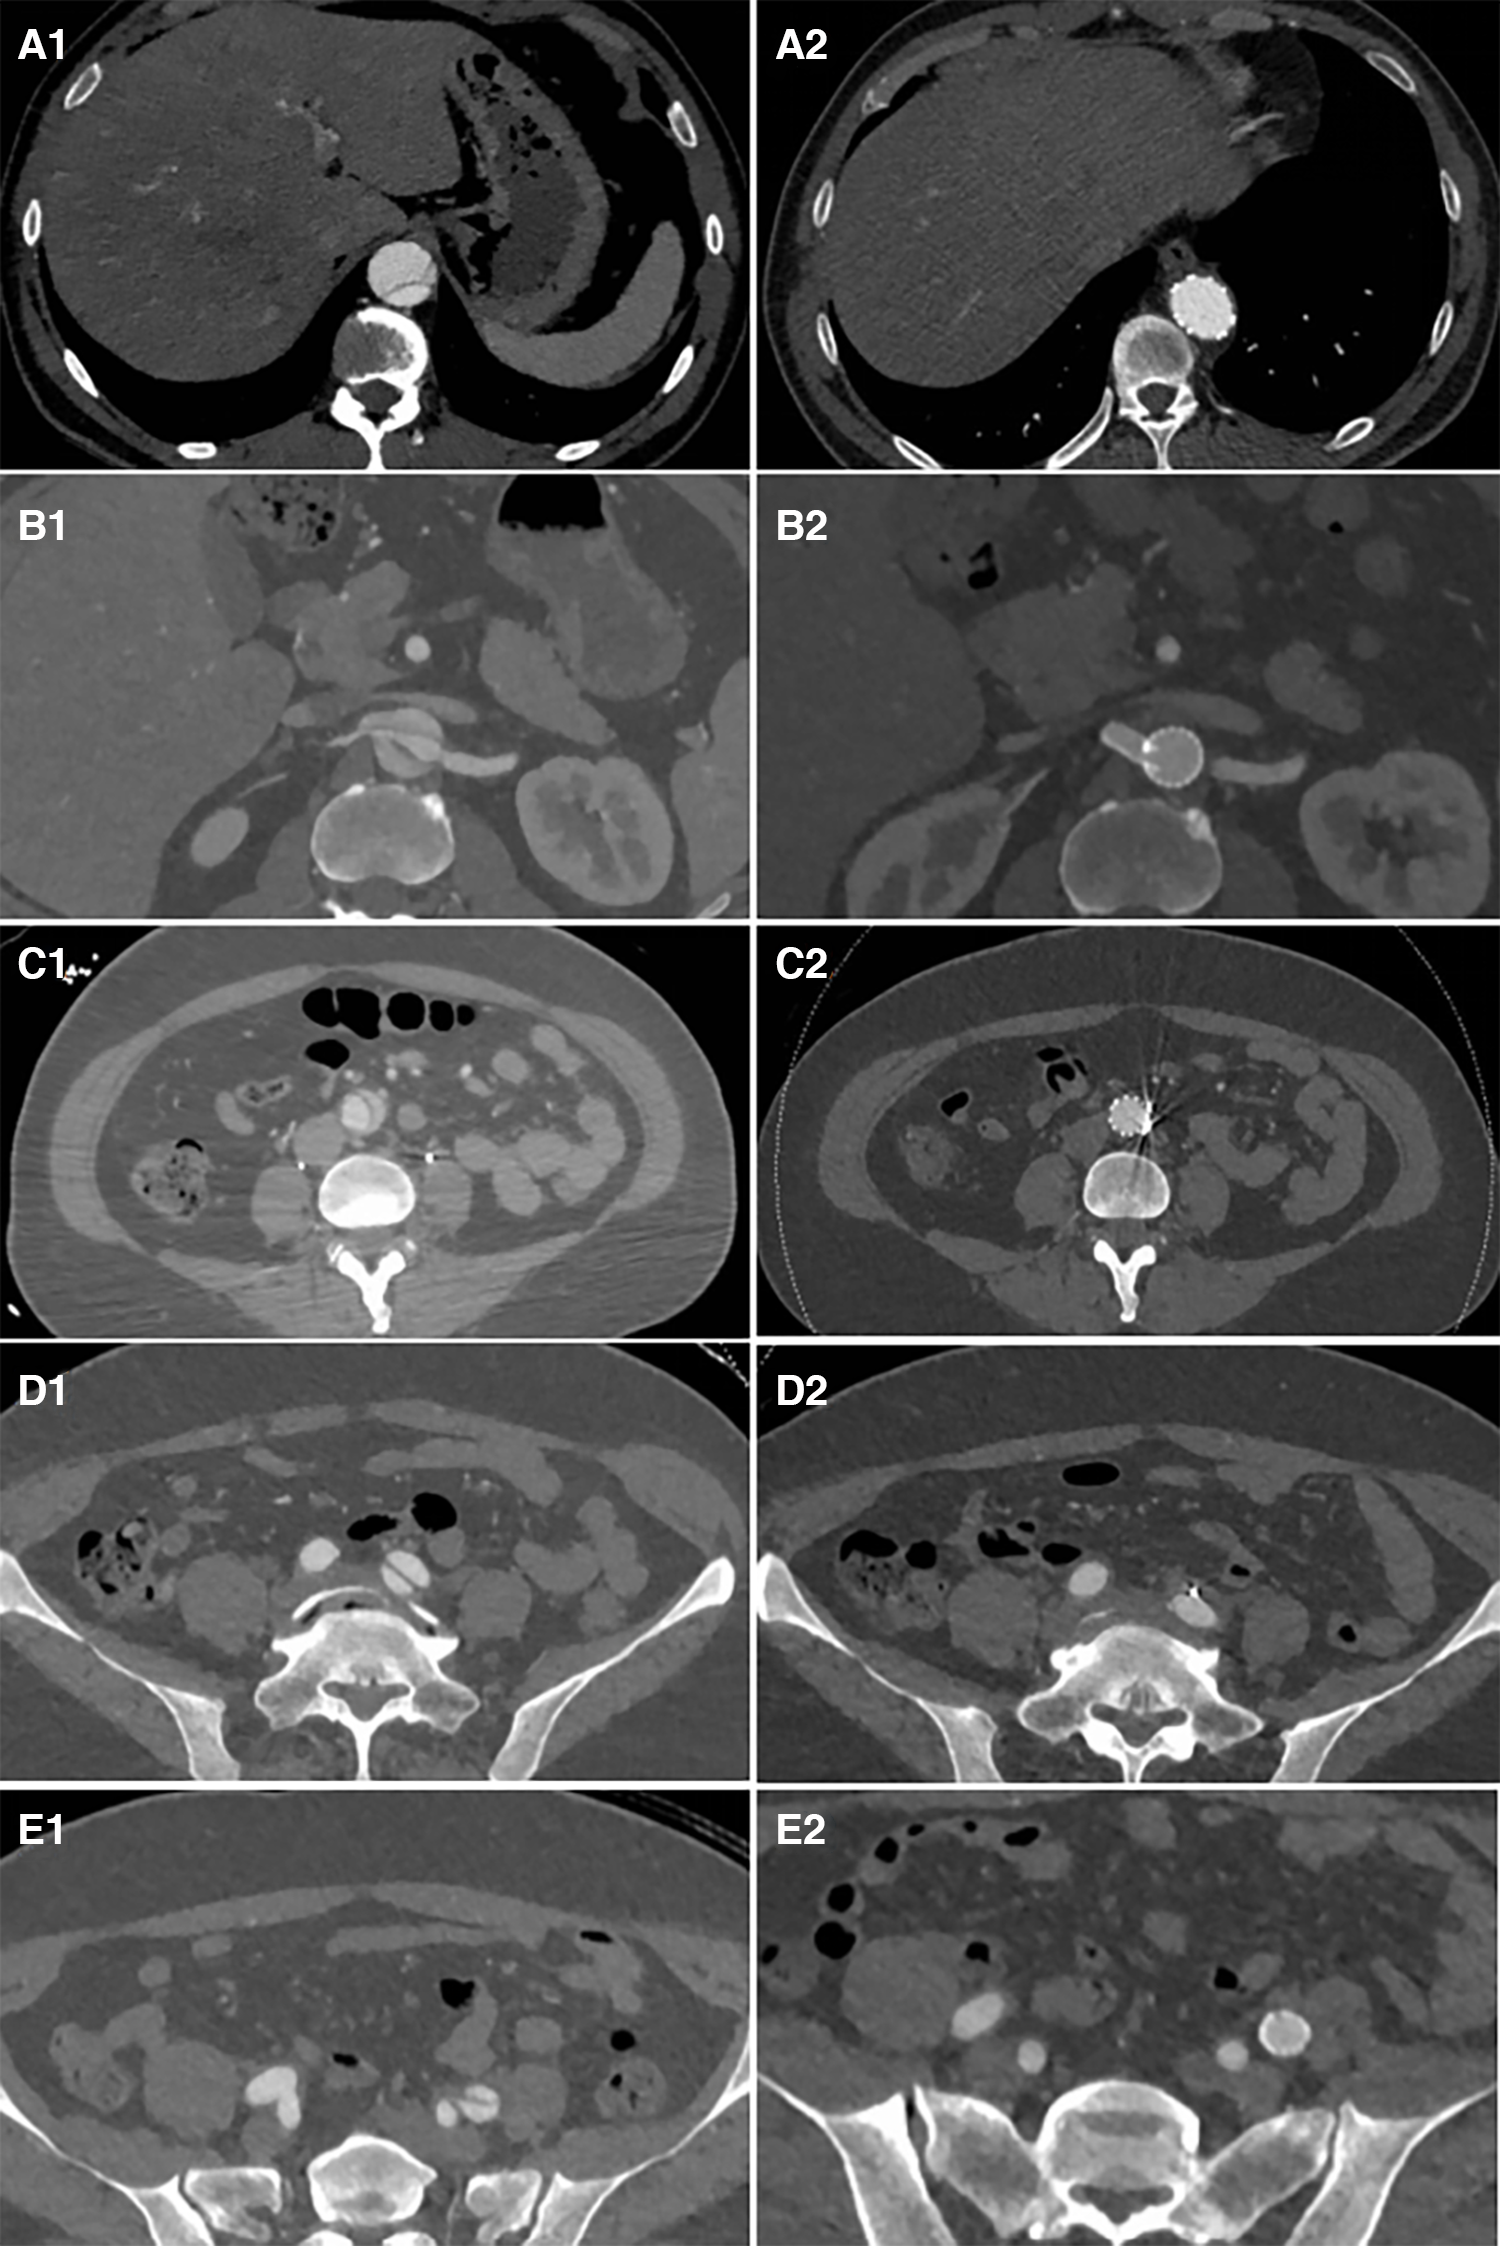

Figure 6

Distal plane of the stent during initial surgery: the TL was narrowed and underwent significant expansion after the second-stage surgery (A1 and A2). The plane of the renal artery opening: After stents were placed in the right renal artery and abdominal artery, the TL of the visceral branch area expanded, and the FL completely disappeared (B1 and B2). The narrowest plane of the TL of the abdominal aorta below the renal artery: Both the TL expanded and the FL disappeared after stent placement (C1 and C2). After the stent placement in the external iliac artery to cover the iliac artery entry tear, the FL disappeared (D1, D2, E1, and E2).